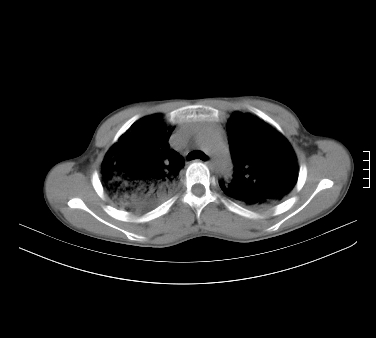

患者,男,17岁,系我院急诊科收治的一例百草枯中毒患者,做ct检查时,距离服药的时间为3天。上传与大家分享

补充:百草枯进入人体内主要分部于肺和骨骼,肺部损伤24小时内出现水肿,2-3天内出现急性呼吸窘迫综合征,1-2周内出现肺纤维化。(引自陈灏珠,实用内科学12版)